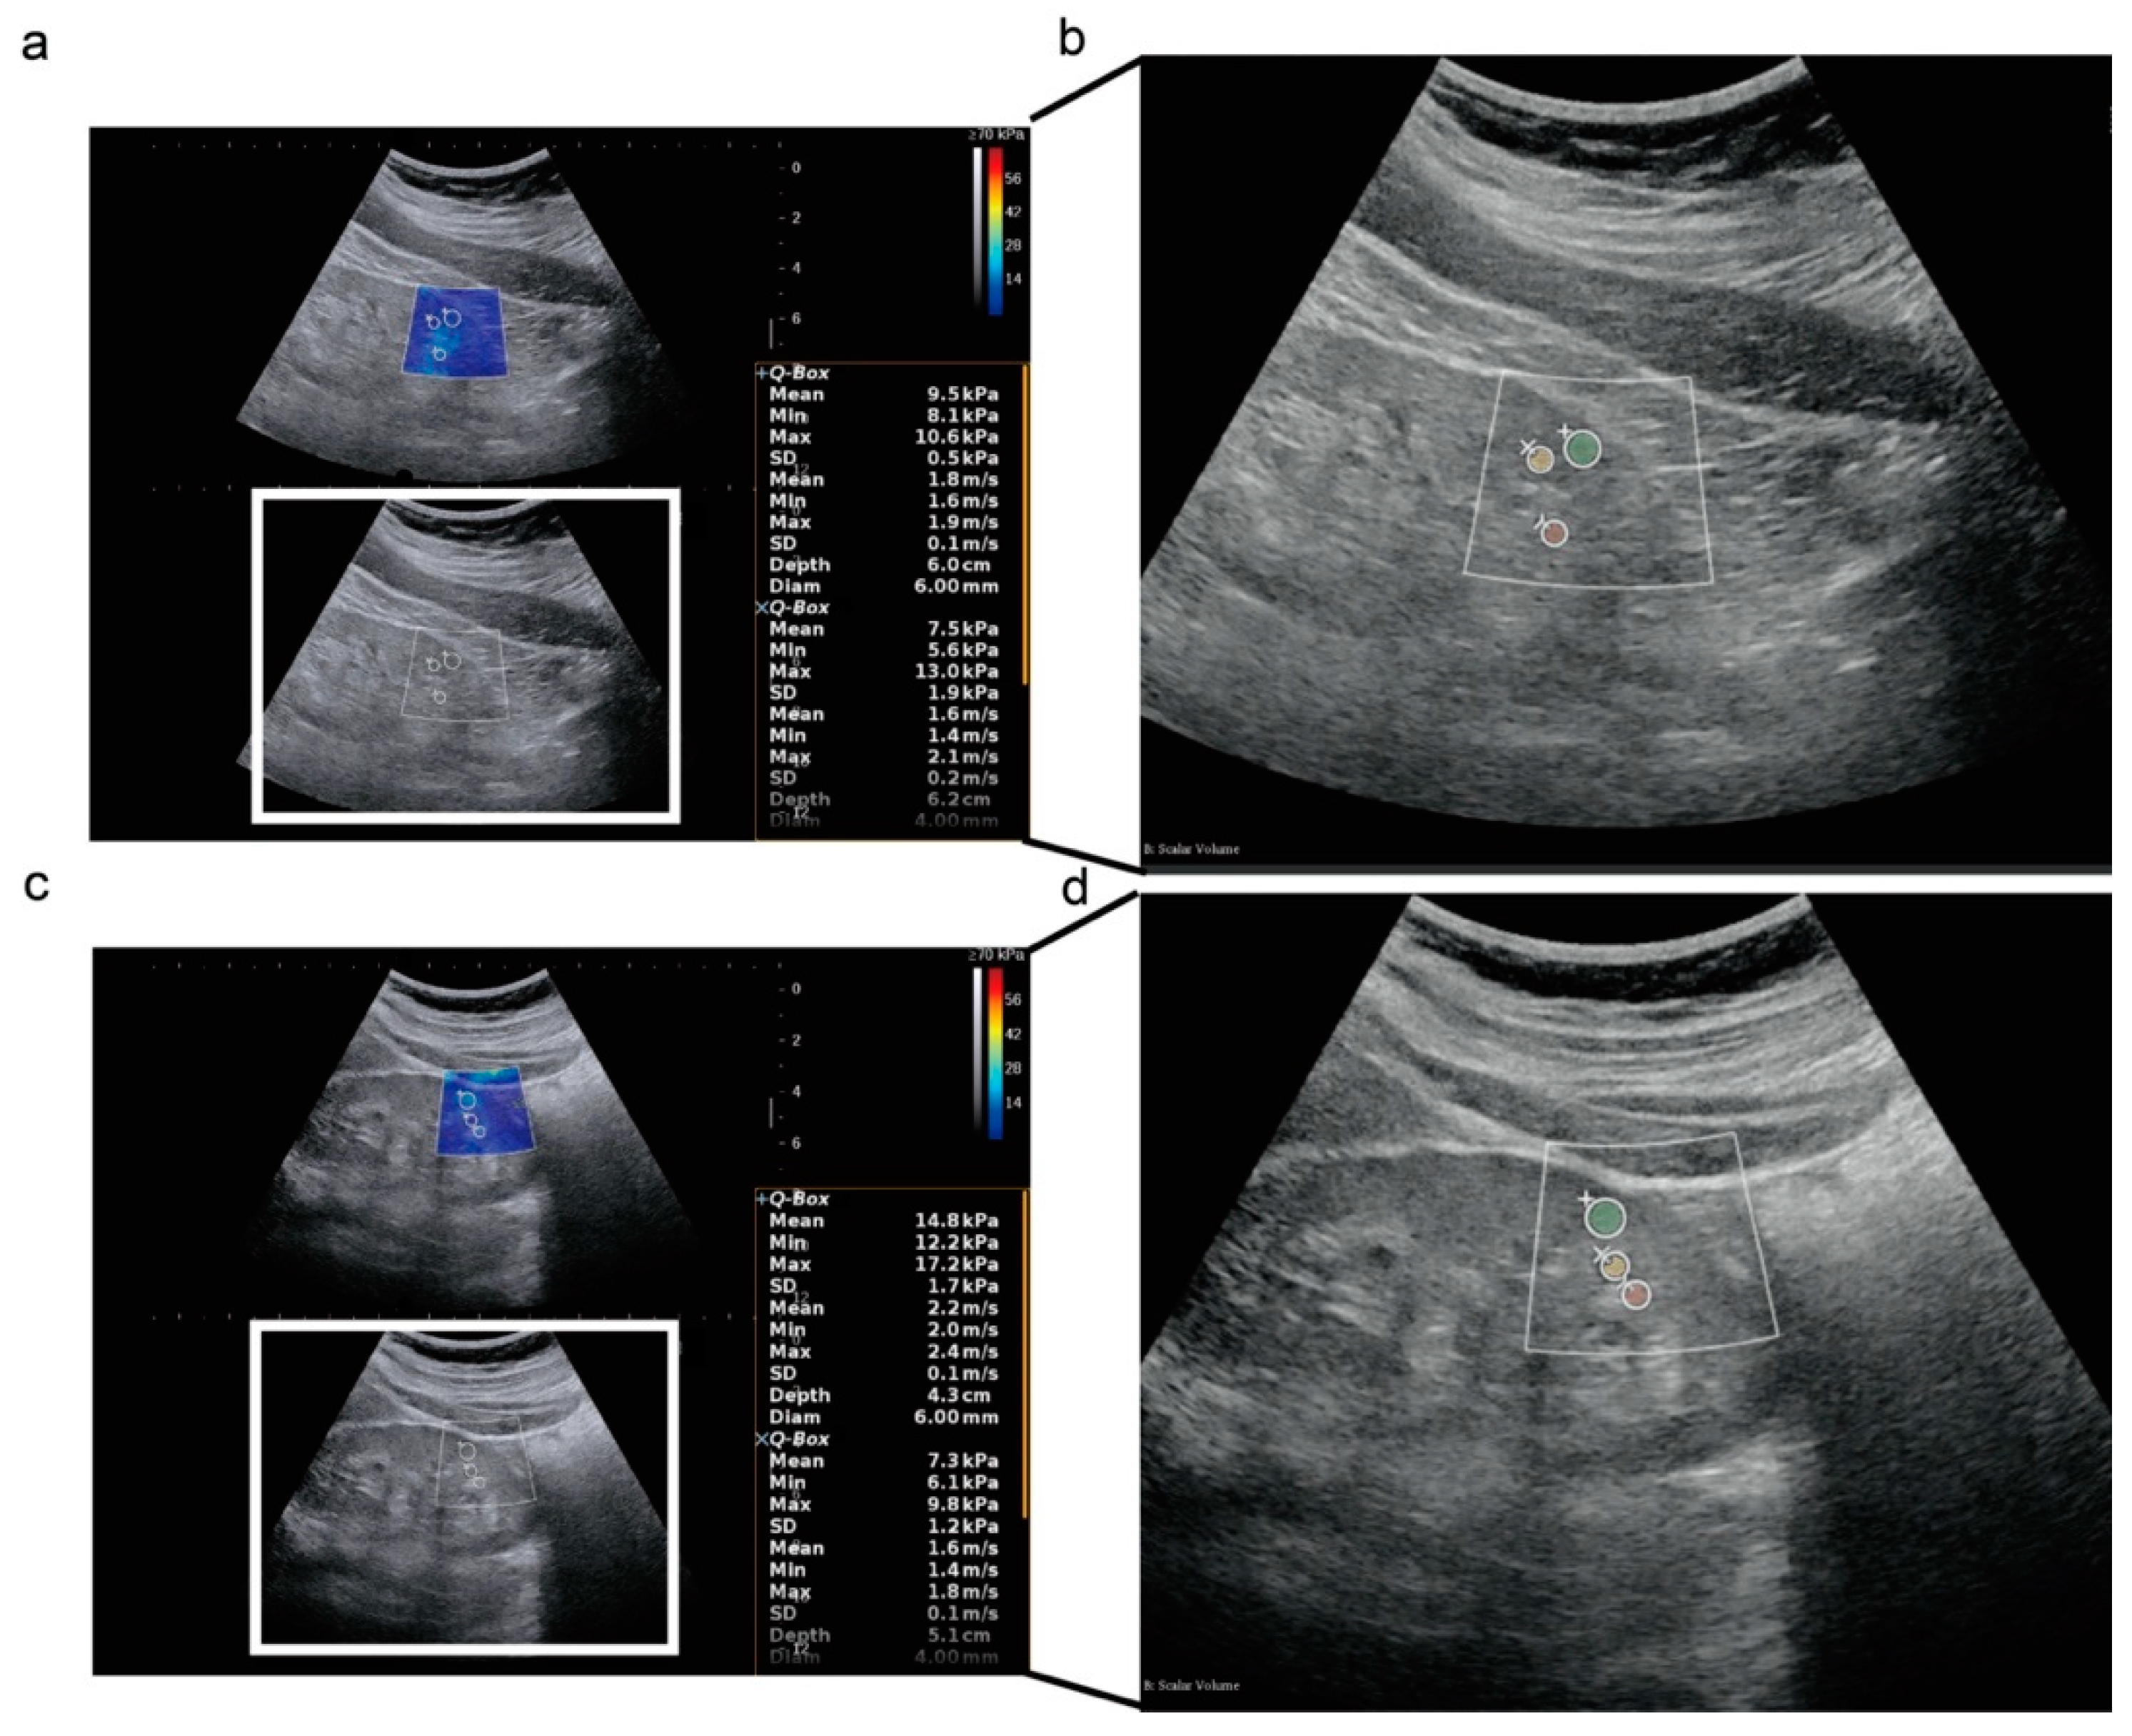

2.2. Clinical, Pathological, and Ultrasound Index

2.3. Radiomics Signature Extraction from Ultrasound